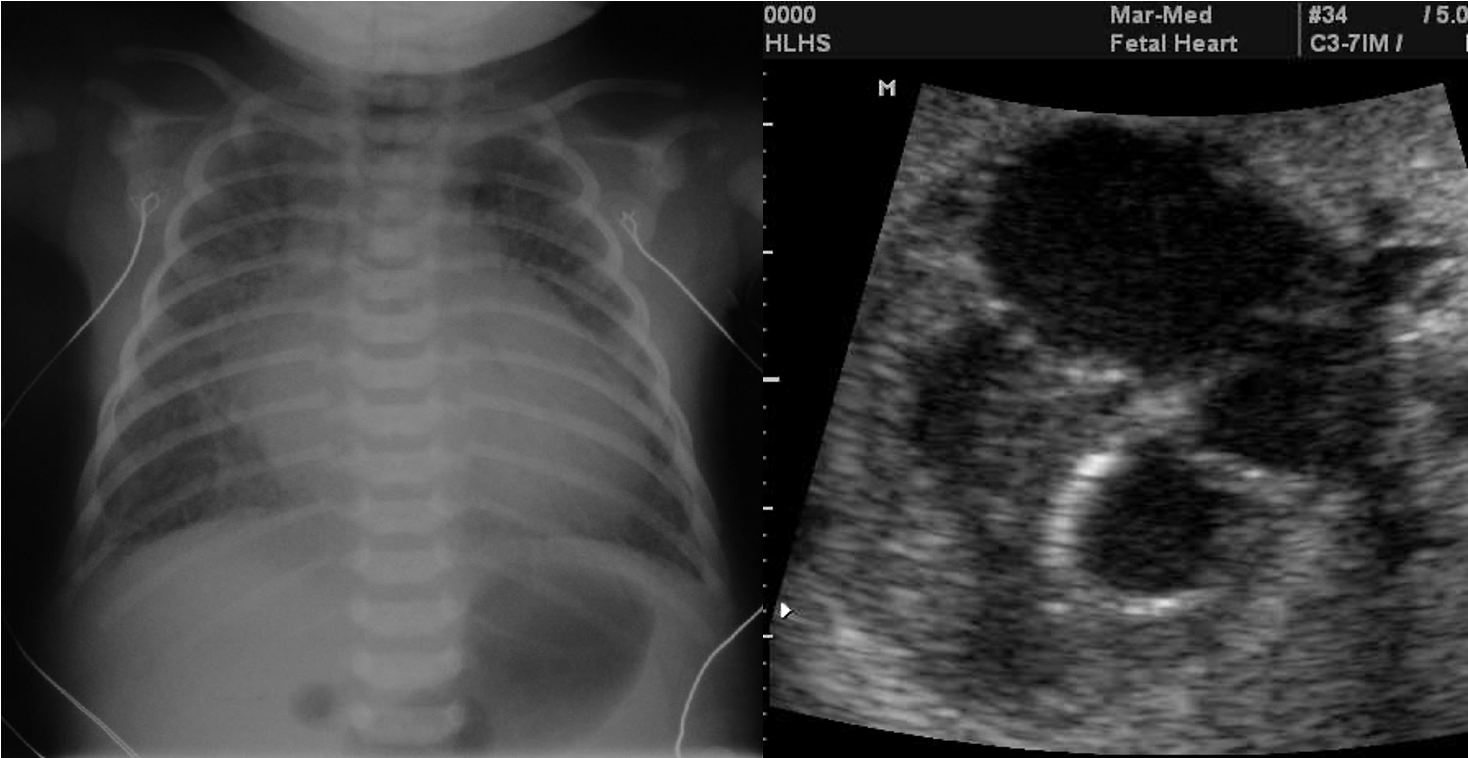

Hypoplastic Left Heart Syndrome